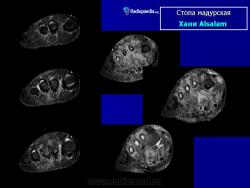

Заболевание прогрессирует как очаговые тканевые образования с формированием опухоли, участков нагноения и рубцов. Иногда формируется множество свищевых ходов, из которых выделяется гной с зернами. Инфекция никогда не распространяется гематогенно, однако может происходить распространение по лимфатическим путям - к региональным лимфатическим узлам и с последующим нагноением. Такие случаи требуют повторных хирургических вмешательств. Вовлеченные ткани могут также вторично загрязняться бактериями. Распространенность поражения мягких тканей лучше всего определять на магнитно-резонансной томографии (МРТ).

Мицетома

Мицетома

Рисунок 21.21

Случаи и цифры